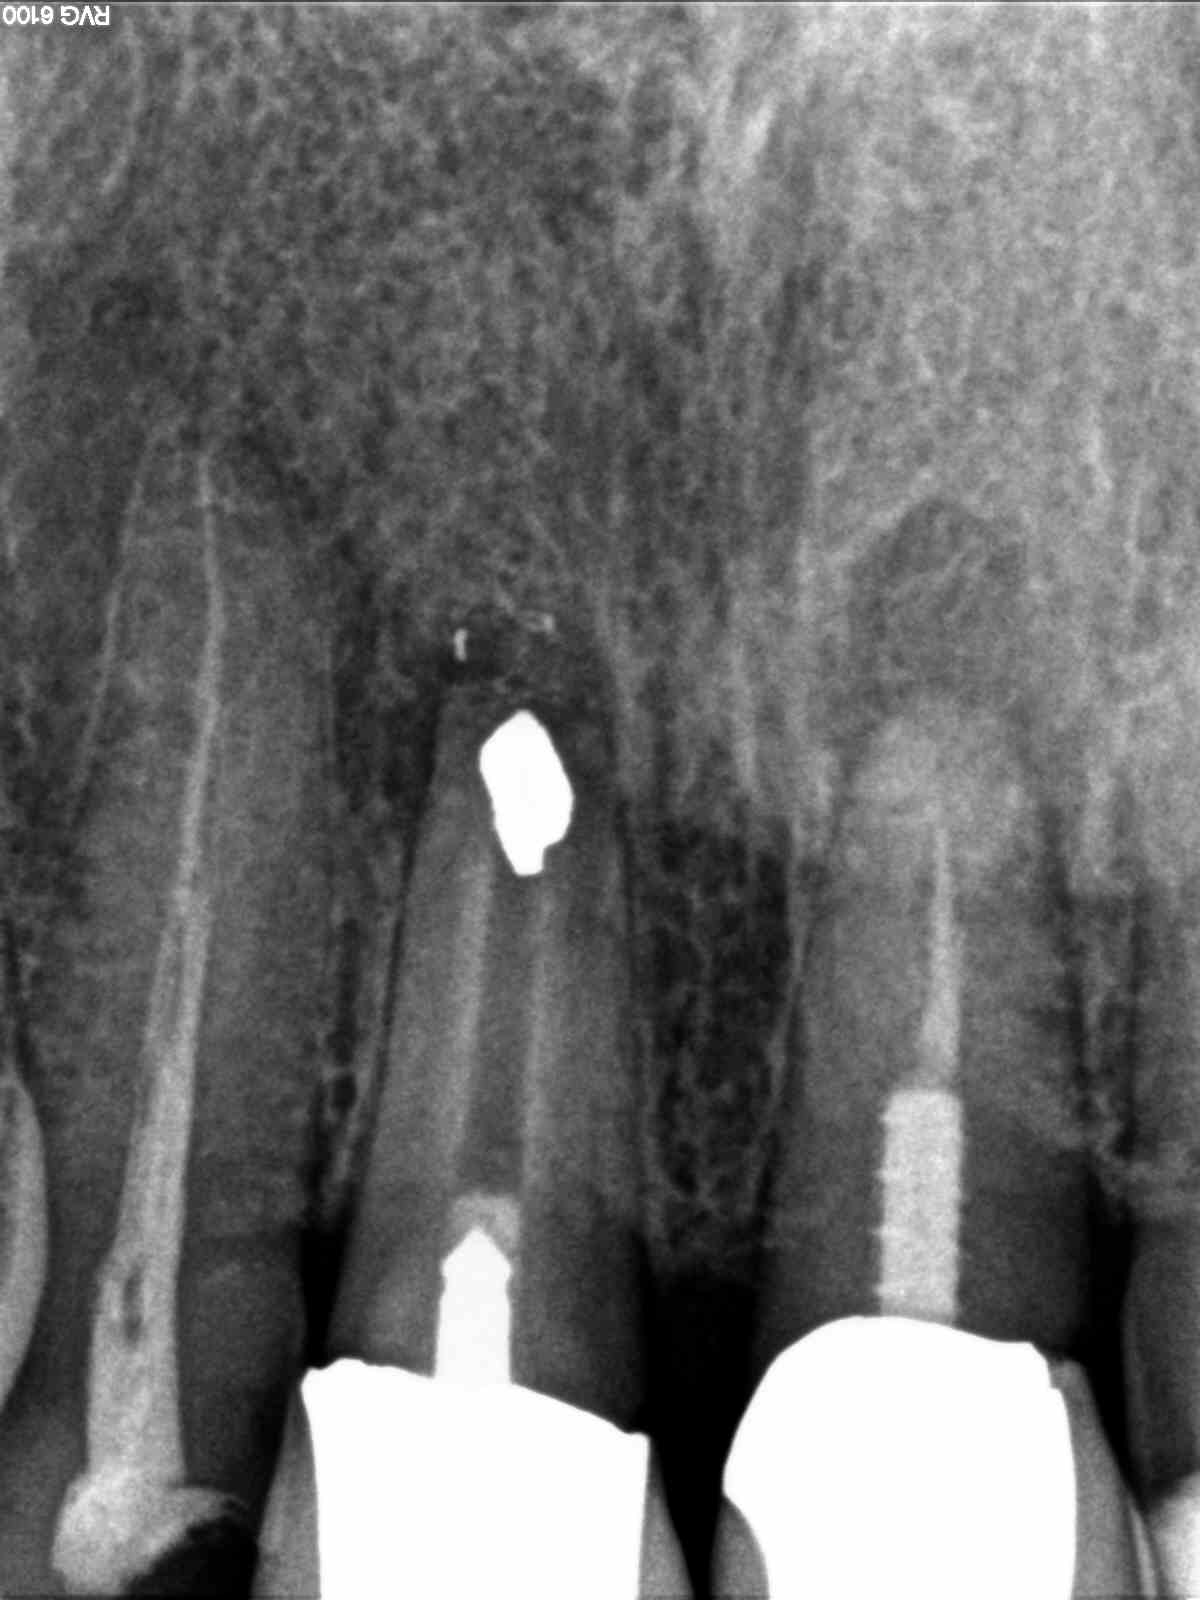

R1

1200 × 1600

Temporärer Stiftaufbau